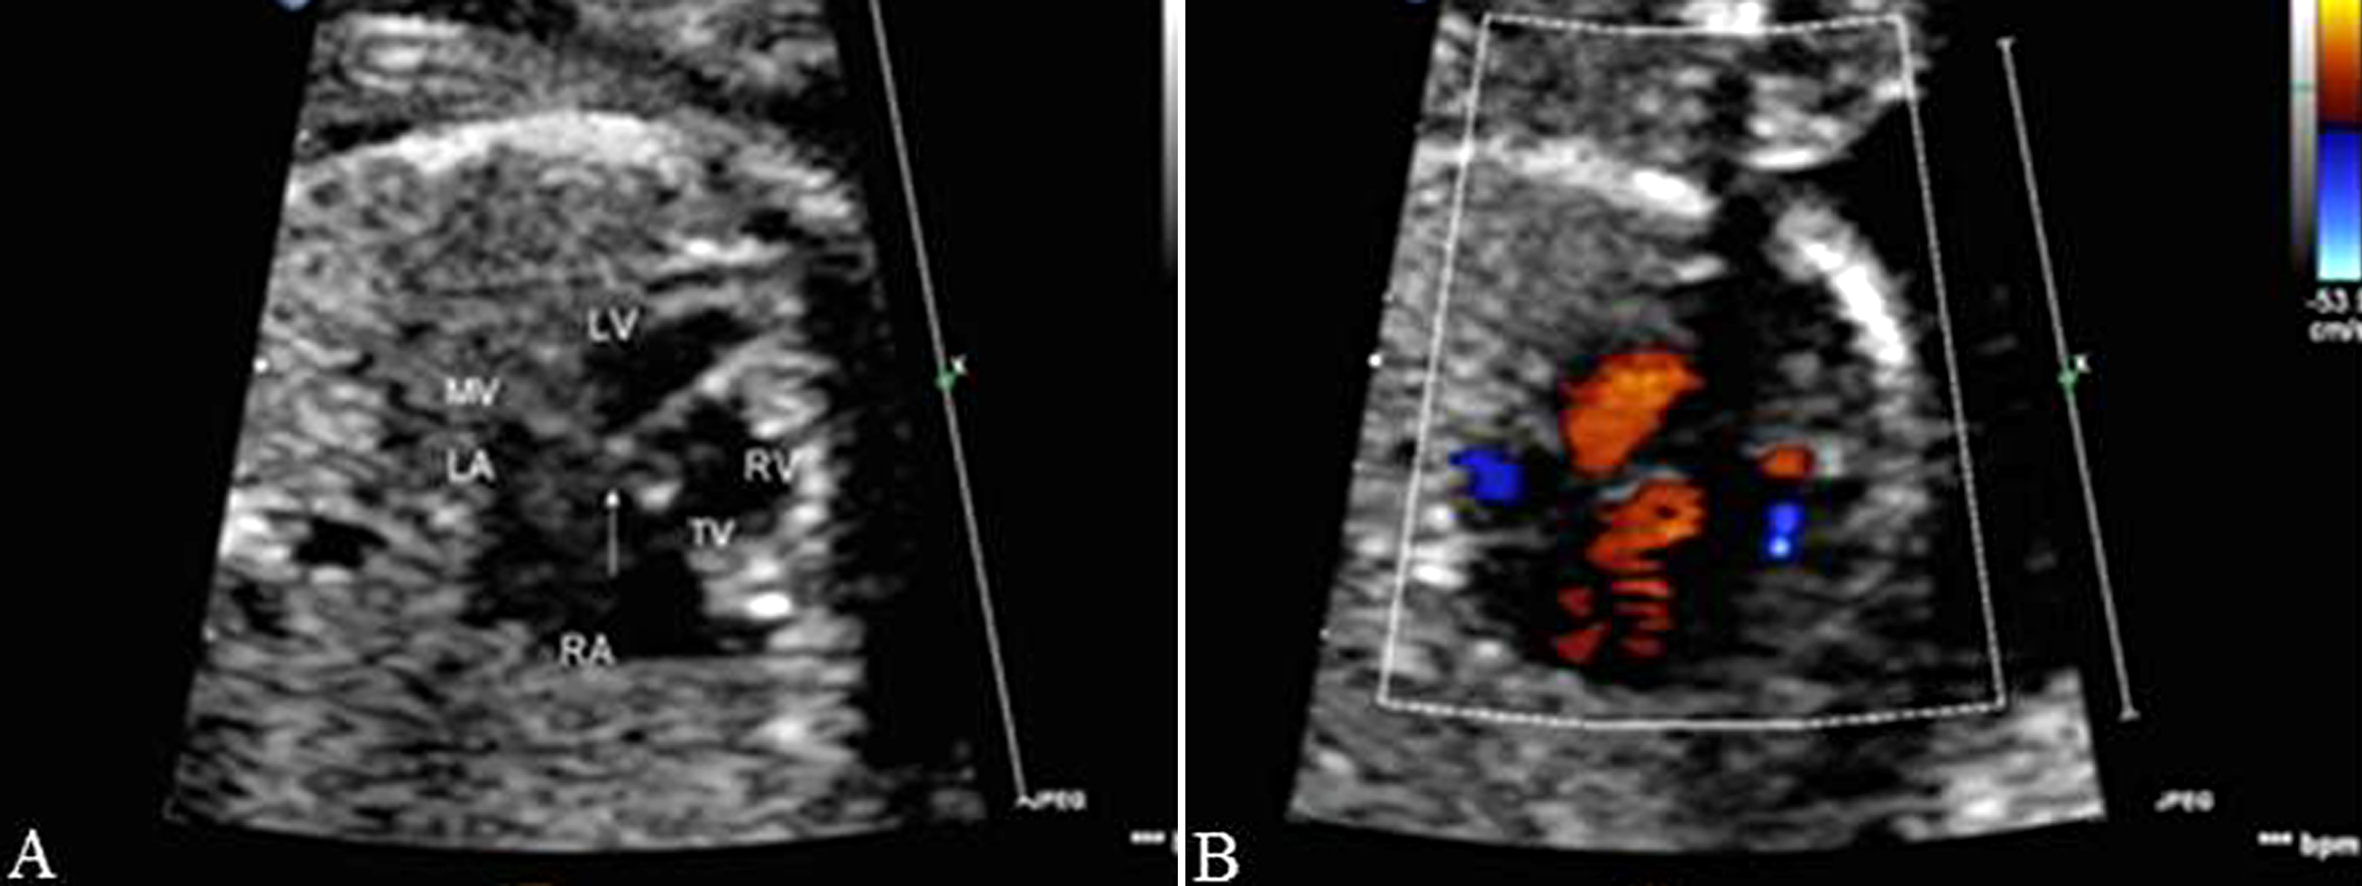

部分性AVSD超声图像特征为:房间隔的原发隔缺失,房室瓣与房室隔十字相交的正常结构消失,二、三尖瓣关闭时呈水平位,同时伴有二尖瓣和(或)三尖瓣反流,而室间隔完整,心室水平无分流(图3)。原发孔型ASD应与增大的冠状静脉窦相鉴别。前者心尖四腔切面观始终无法显示正常的十字交叉结构,后者声束在心尖四腔切面观靠后时显示等号状增大的冠状静脉窦,同时不能显示二尖瓣,而心尖四腔切面观时可见正常的十字交叉结构,并可见左侧房室沟处呈环状增大的冠状静脉窦(图4);另外,冠状静脉窦增宽常合并左侧上腔静脉永存,三血管气管切面在肺动脉左侧可见与右侧上腔静脉对称的血管即左侧上腔静脉(图5)。

图3 胎儿部分性房室间隔缺损

图4 胎儿冠状静脉窦增宽